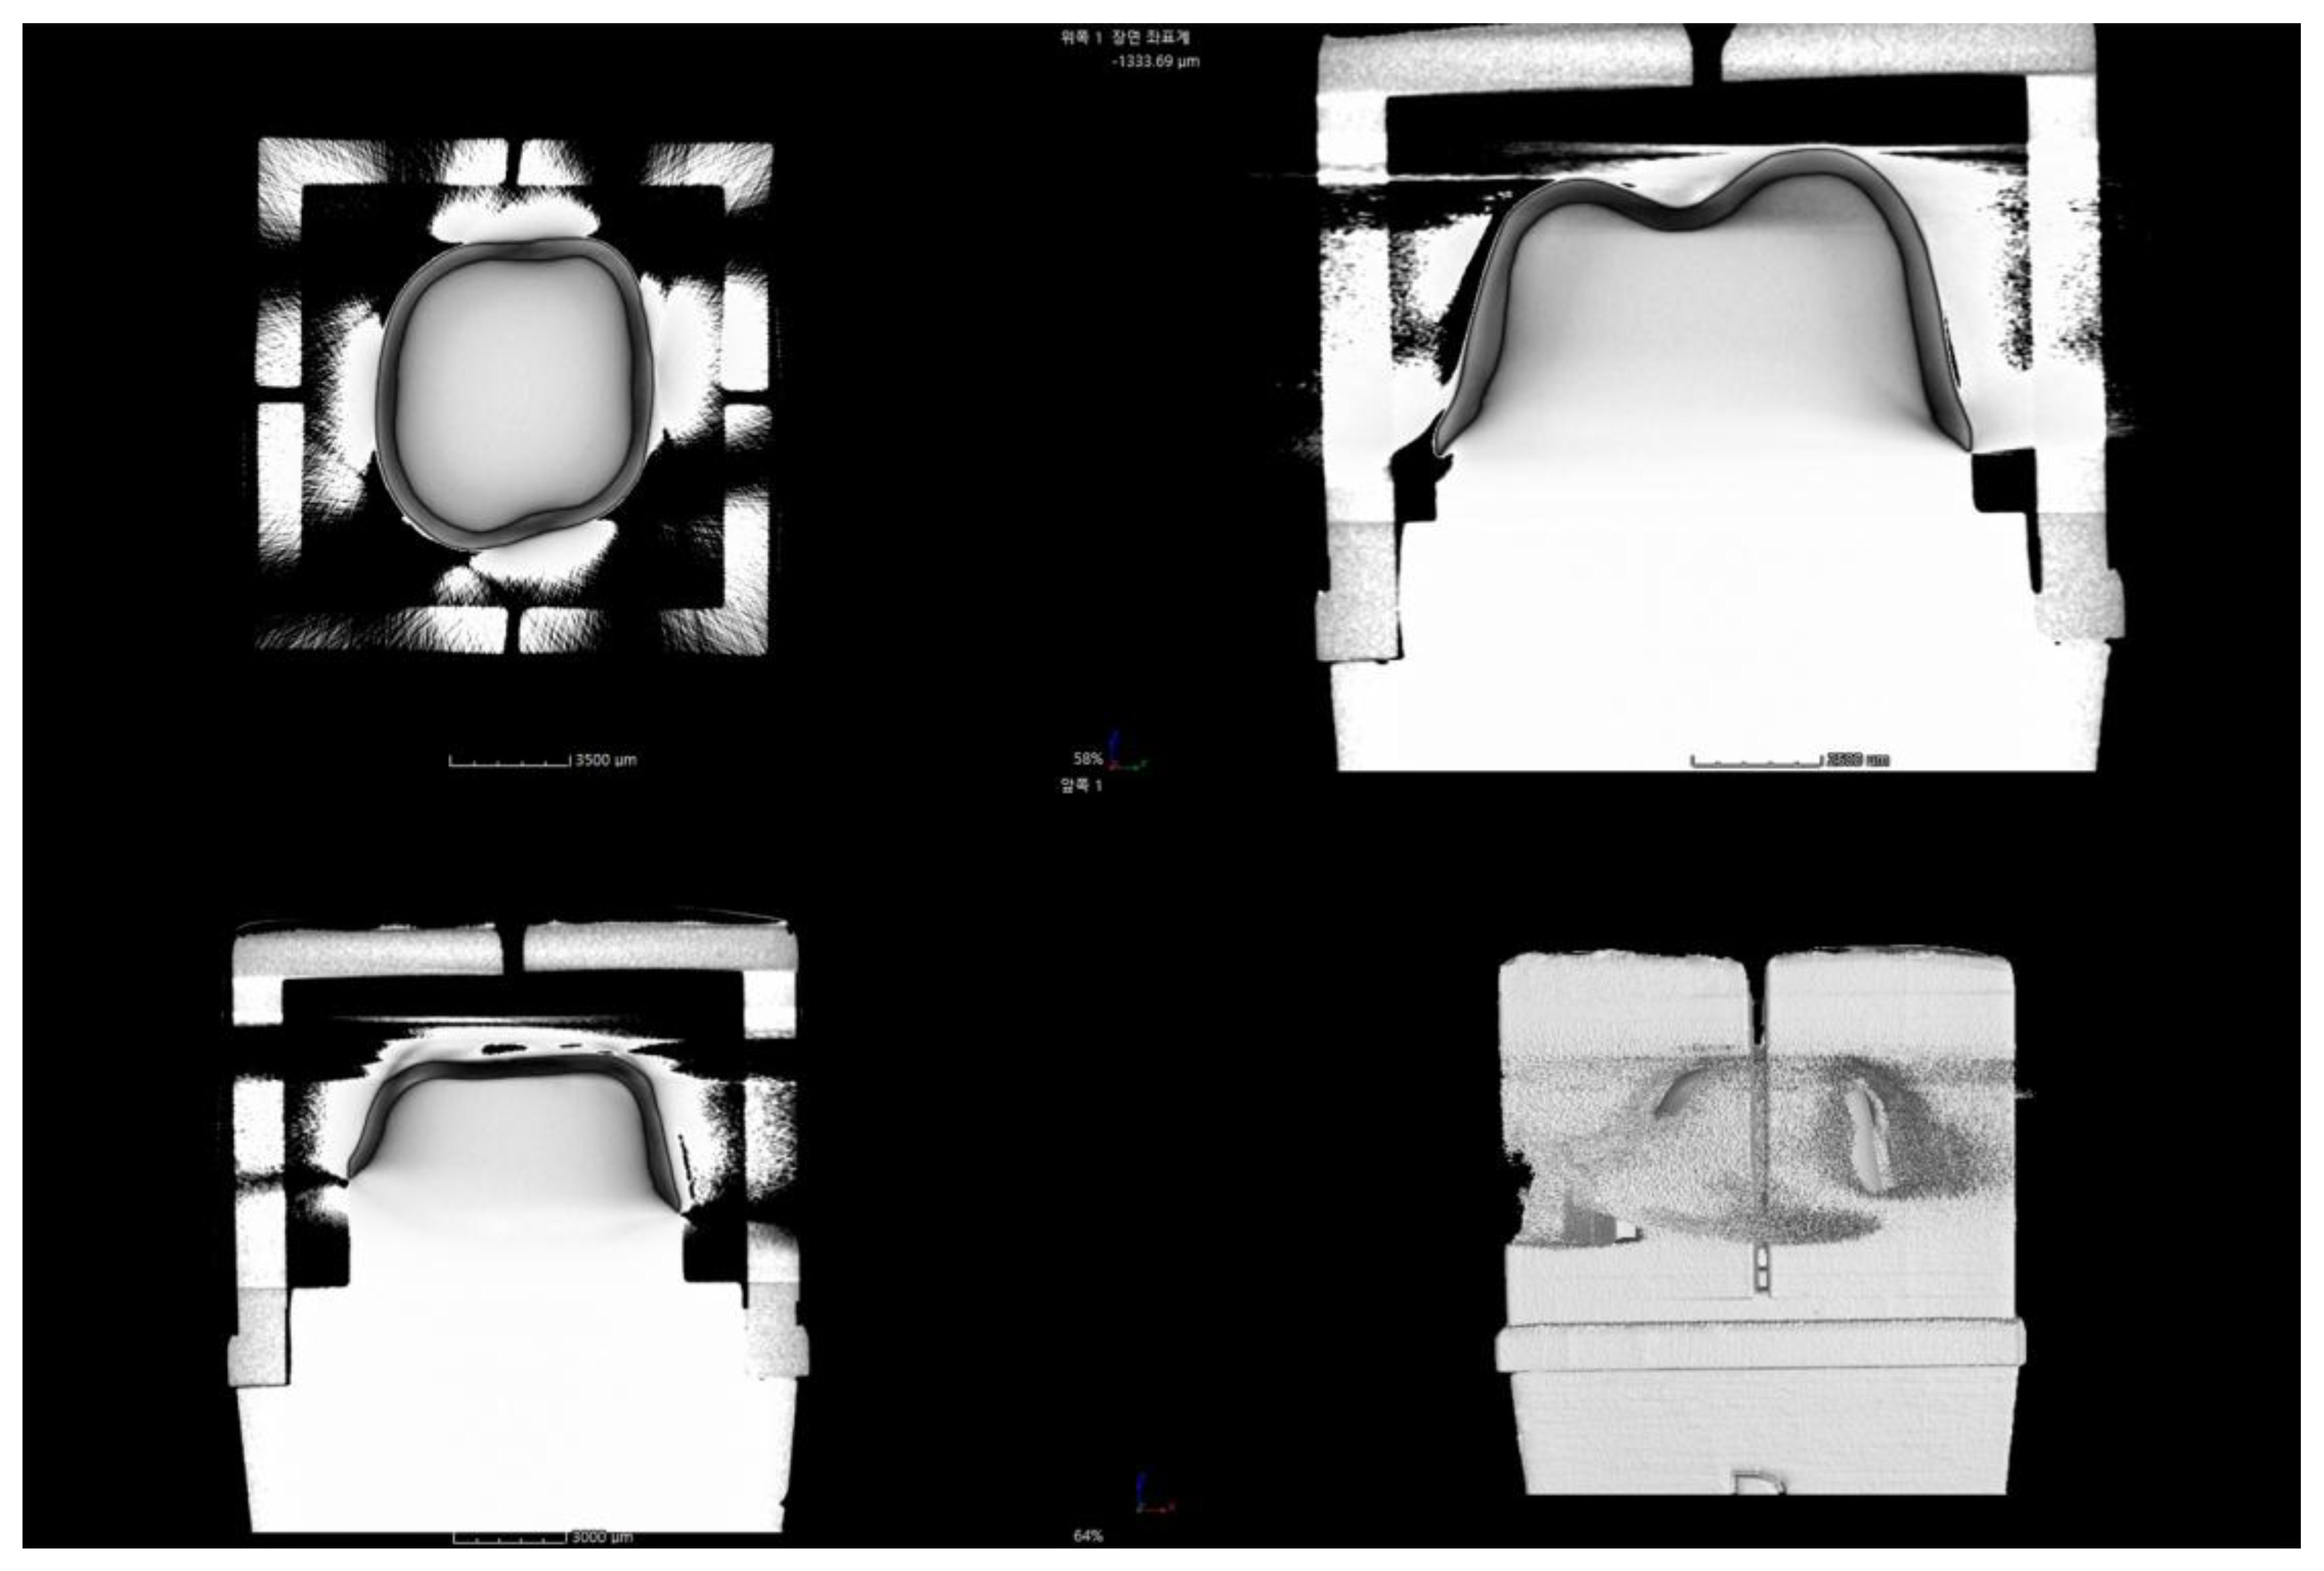

- Micro-computed tomography (MCT): MCT measures the internal and marginal fit of the prosthesis using radiography. The merits of this method include a high resolution and the ability to measure the desired parts by obtaining 3D images. However, the disadvantages of this method include the difficulty to measure metallic prostheses due to the presence of artifacts and an increased risk of exposure to radiation [3,4,13,14,15,21,36].

2.2.4. Micro-Computed Tomography (MCT Group)